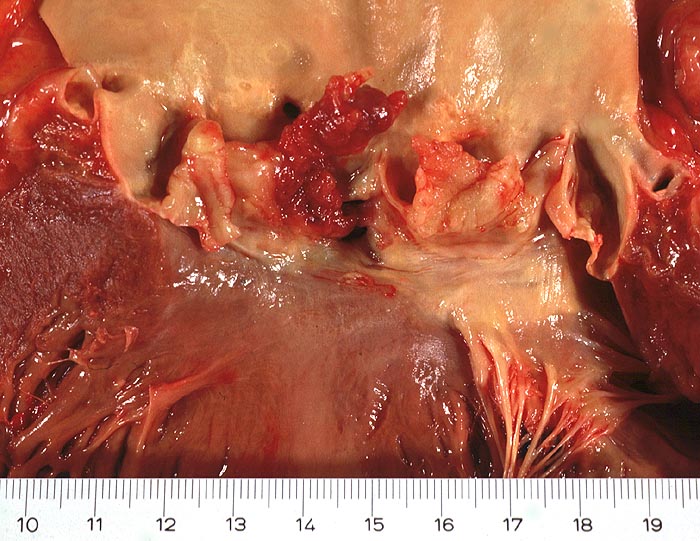

Makroskopisch sind entweder flache rötliche fibrinbelegte Ulzera (=ulcerosa (> 2935)) oder zusätzlich weiche gelbbraune bröcklige erbs- bis pflaumengrosse Polypen (=ulceropolyposa (> 2936) (> 8376)) oder ausschliesslich polypoide Fibrinbeläge (=marantica) auf einem Endokarddefekt oder einer partiell zerstörten Klappe erkennbar.

Histologisch findet sich bei ulzeropolypöser Endokarditis ein Fibrin-Thrombozytenthrombus, welcher von Bakterien durchsetzt ist (=Vegetation). Die Vegetation sitzt auf einem Klappendefekt an dessen Basis Granulationsgewebe einzusprossen beginnt, welches den Thrombus organisiert. Klappendefekte, Gefässeinsprossungen, verdickte Sehnenfäden (> 2848) oder Kommissurenverwachsungen (> 8389) der Taschenklappen weisen morphologisch auf eine abgeheilte Endokarditis hin.

Mögliche Komplikationen einer infektiösen Endokarditis sind Klappenperforation (> 2934) oder Sehnenfadenruptur mit akuter Klappeninsuffizienz, Klappenstenose durch grosse Vegetationen, Übergreifen der Entzündung auf das Myokard, Dehiszenz von Klappenprothesen, Klappenvitium, Sepsis, septische (> 2120) oder sterile, häufig zerebrale Embolien, mykotisches Aneurysma und Glomerulonephritis.